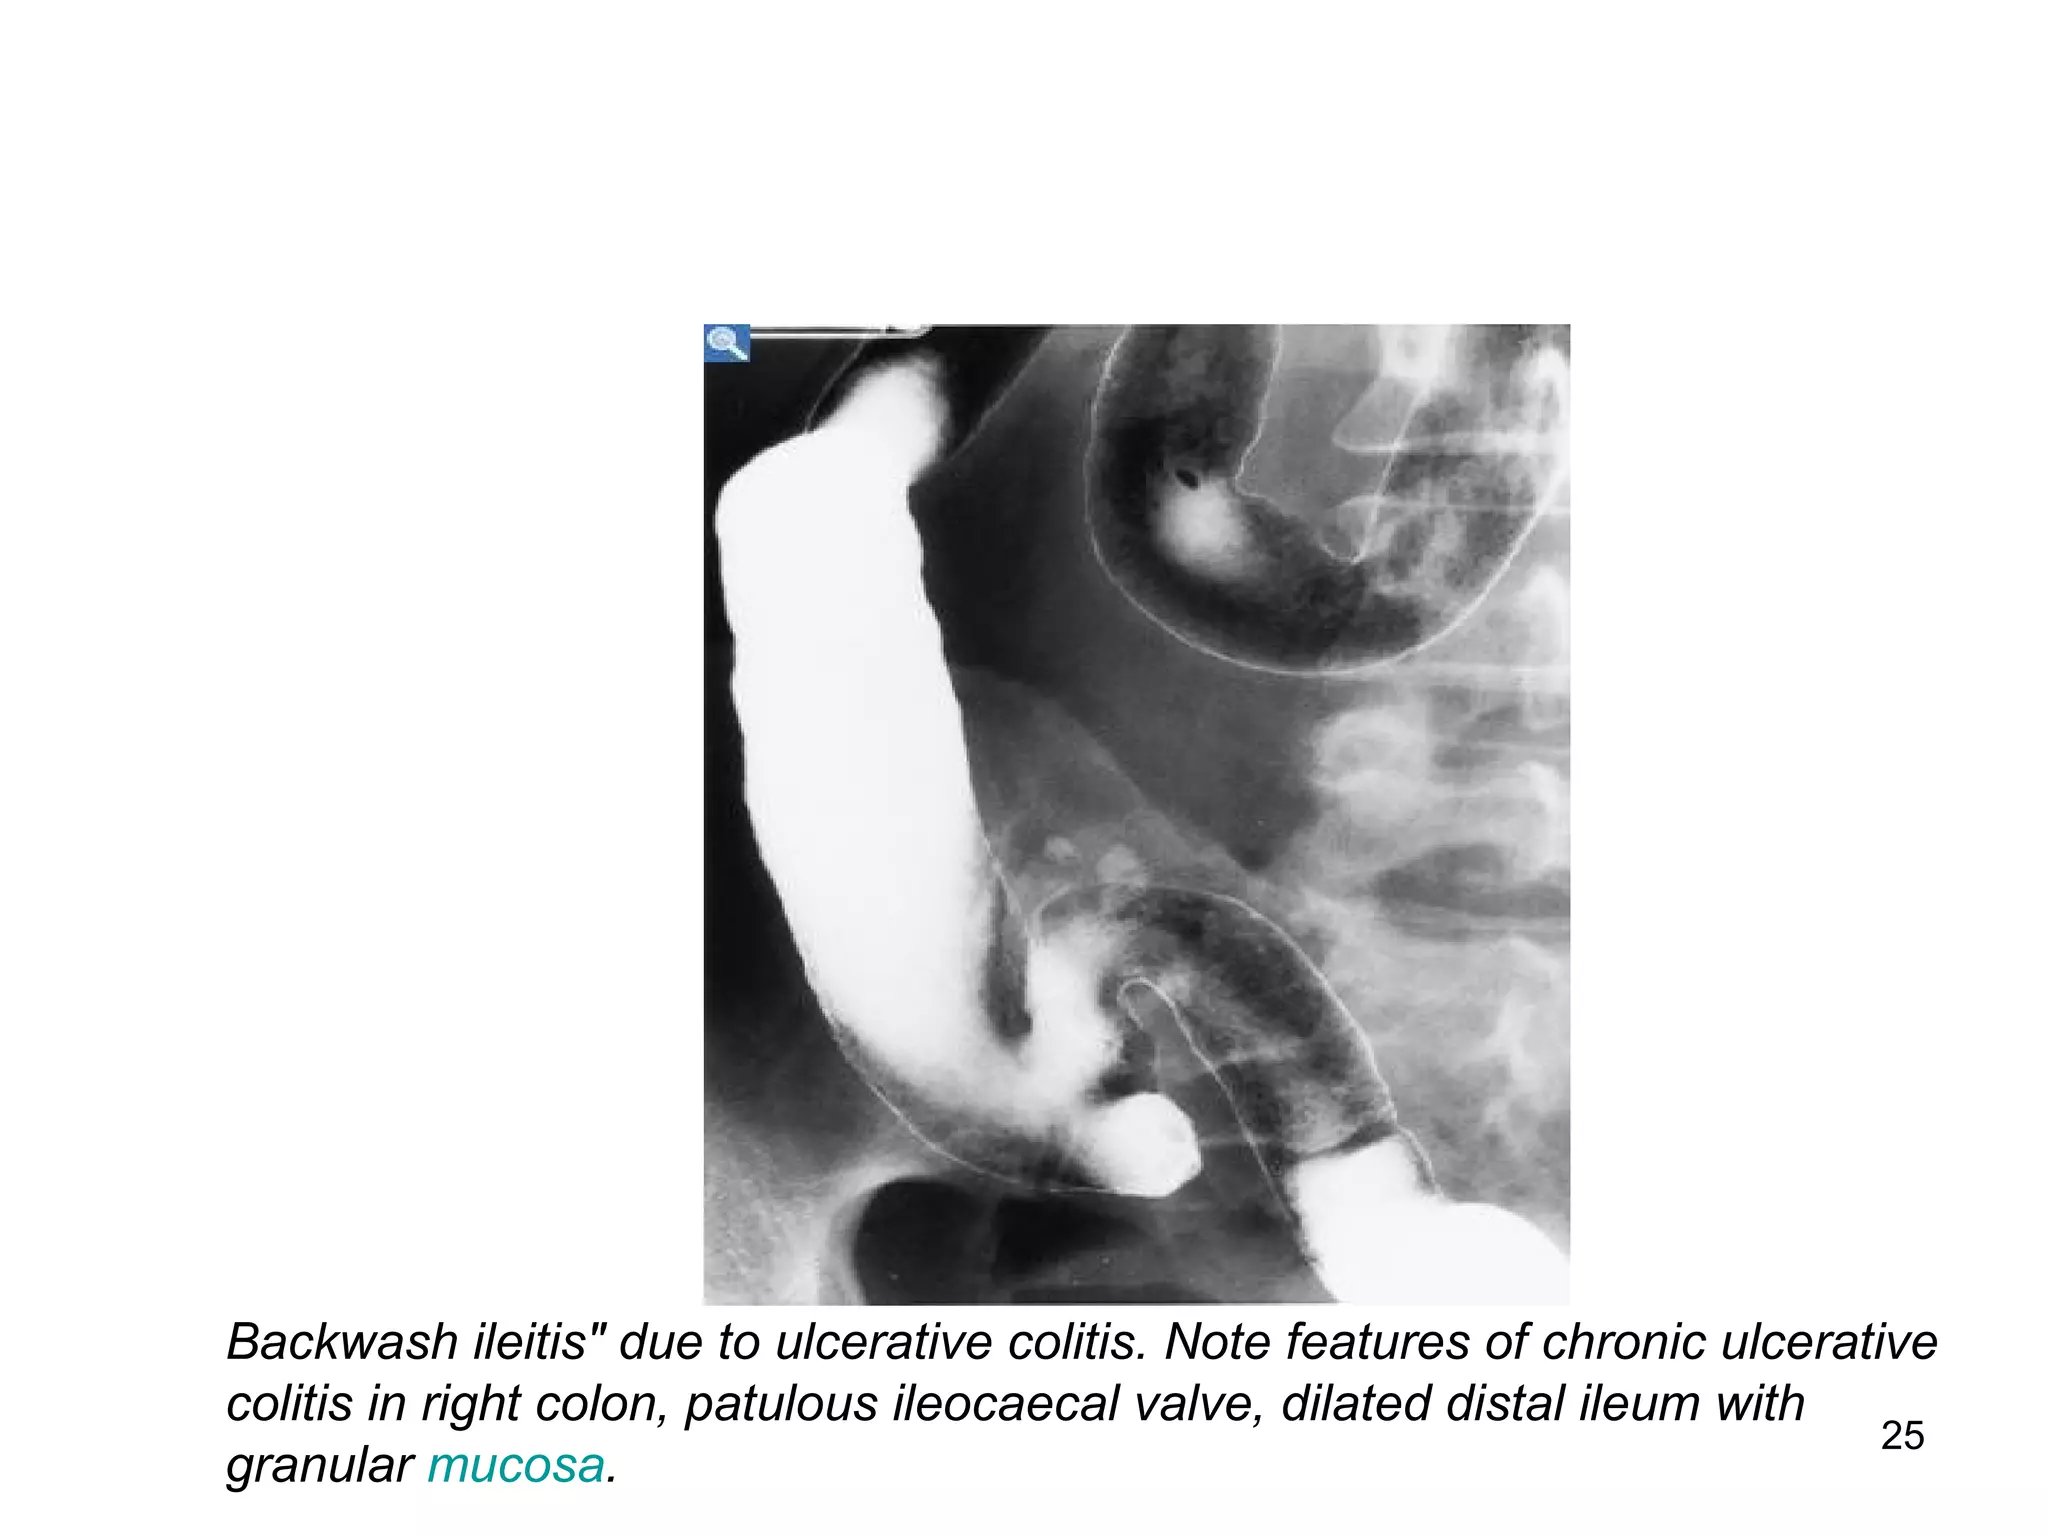

Backwash ileitis" due to ulcerative colitis. Note features of chronic ulcerative

colitis in right colon, patulous ileocaecal valve, dilated distal ileum with

granular mucosa.

25 Backwash ileitis" dueto ulcerative colitis. Note features of chronic ulcerative colitis in right colon, patulous ileocaecal valve, dilated distal ileum with granular mucosa.